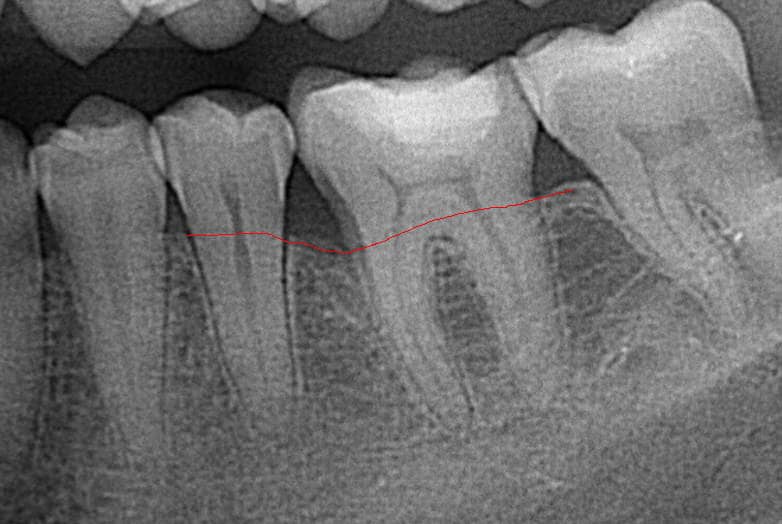

The following image shows the regeneration of bone tissue six months after the regenerative surgery.